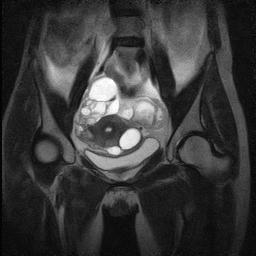

Здоровье женщин: МРТ при цистаденофиброме яичника